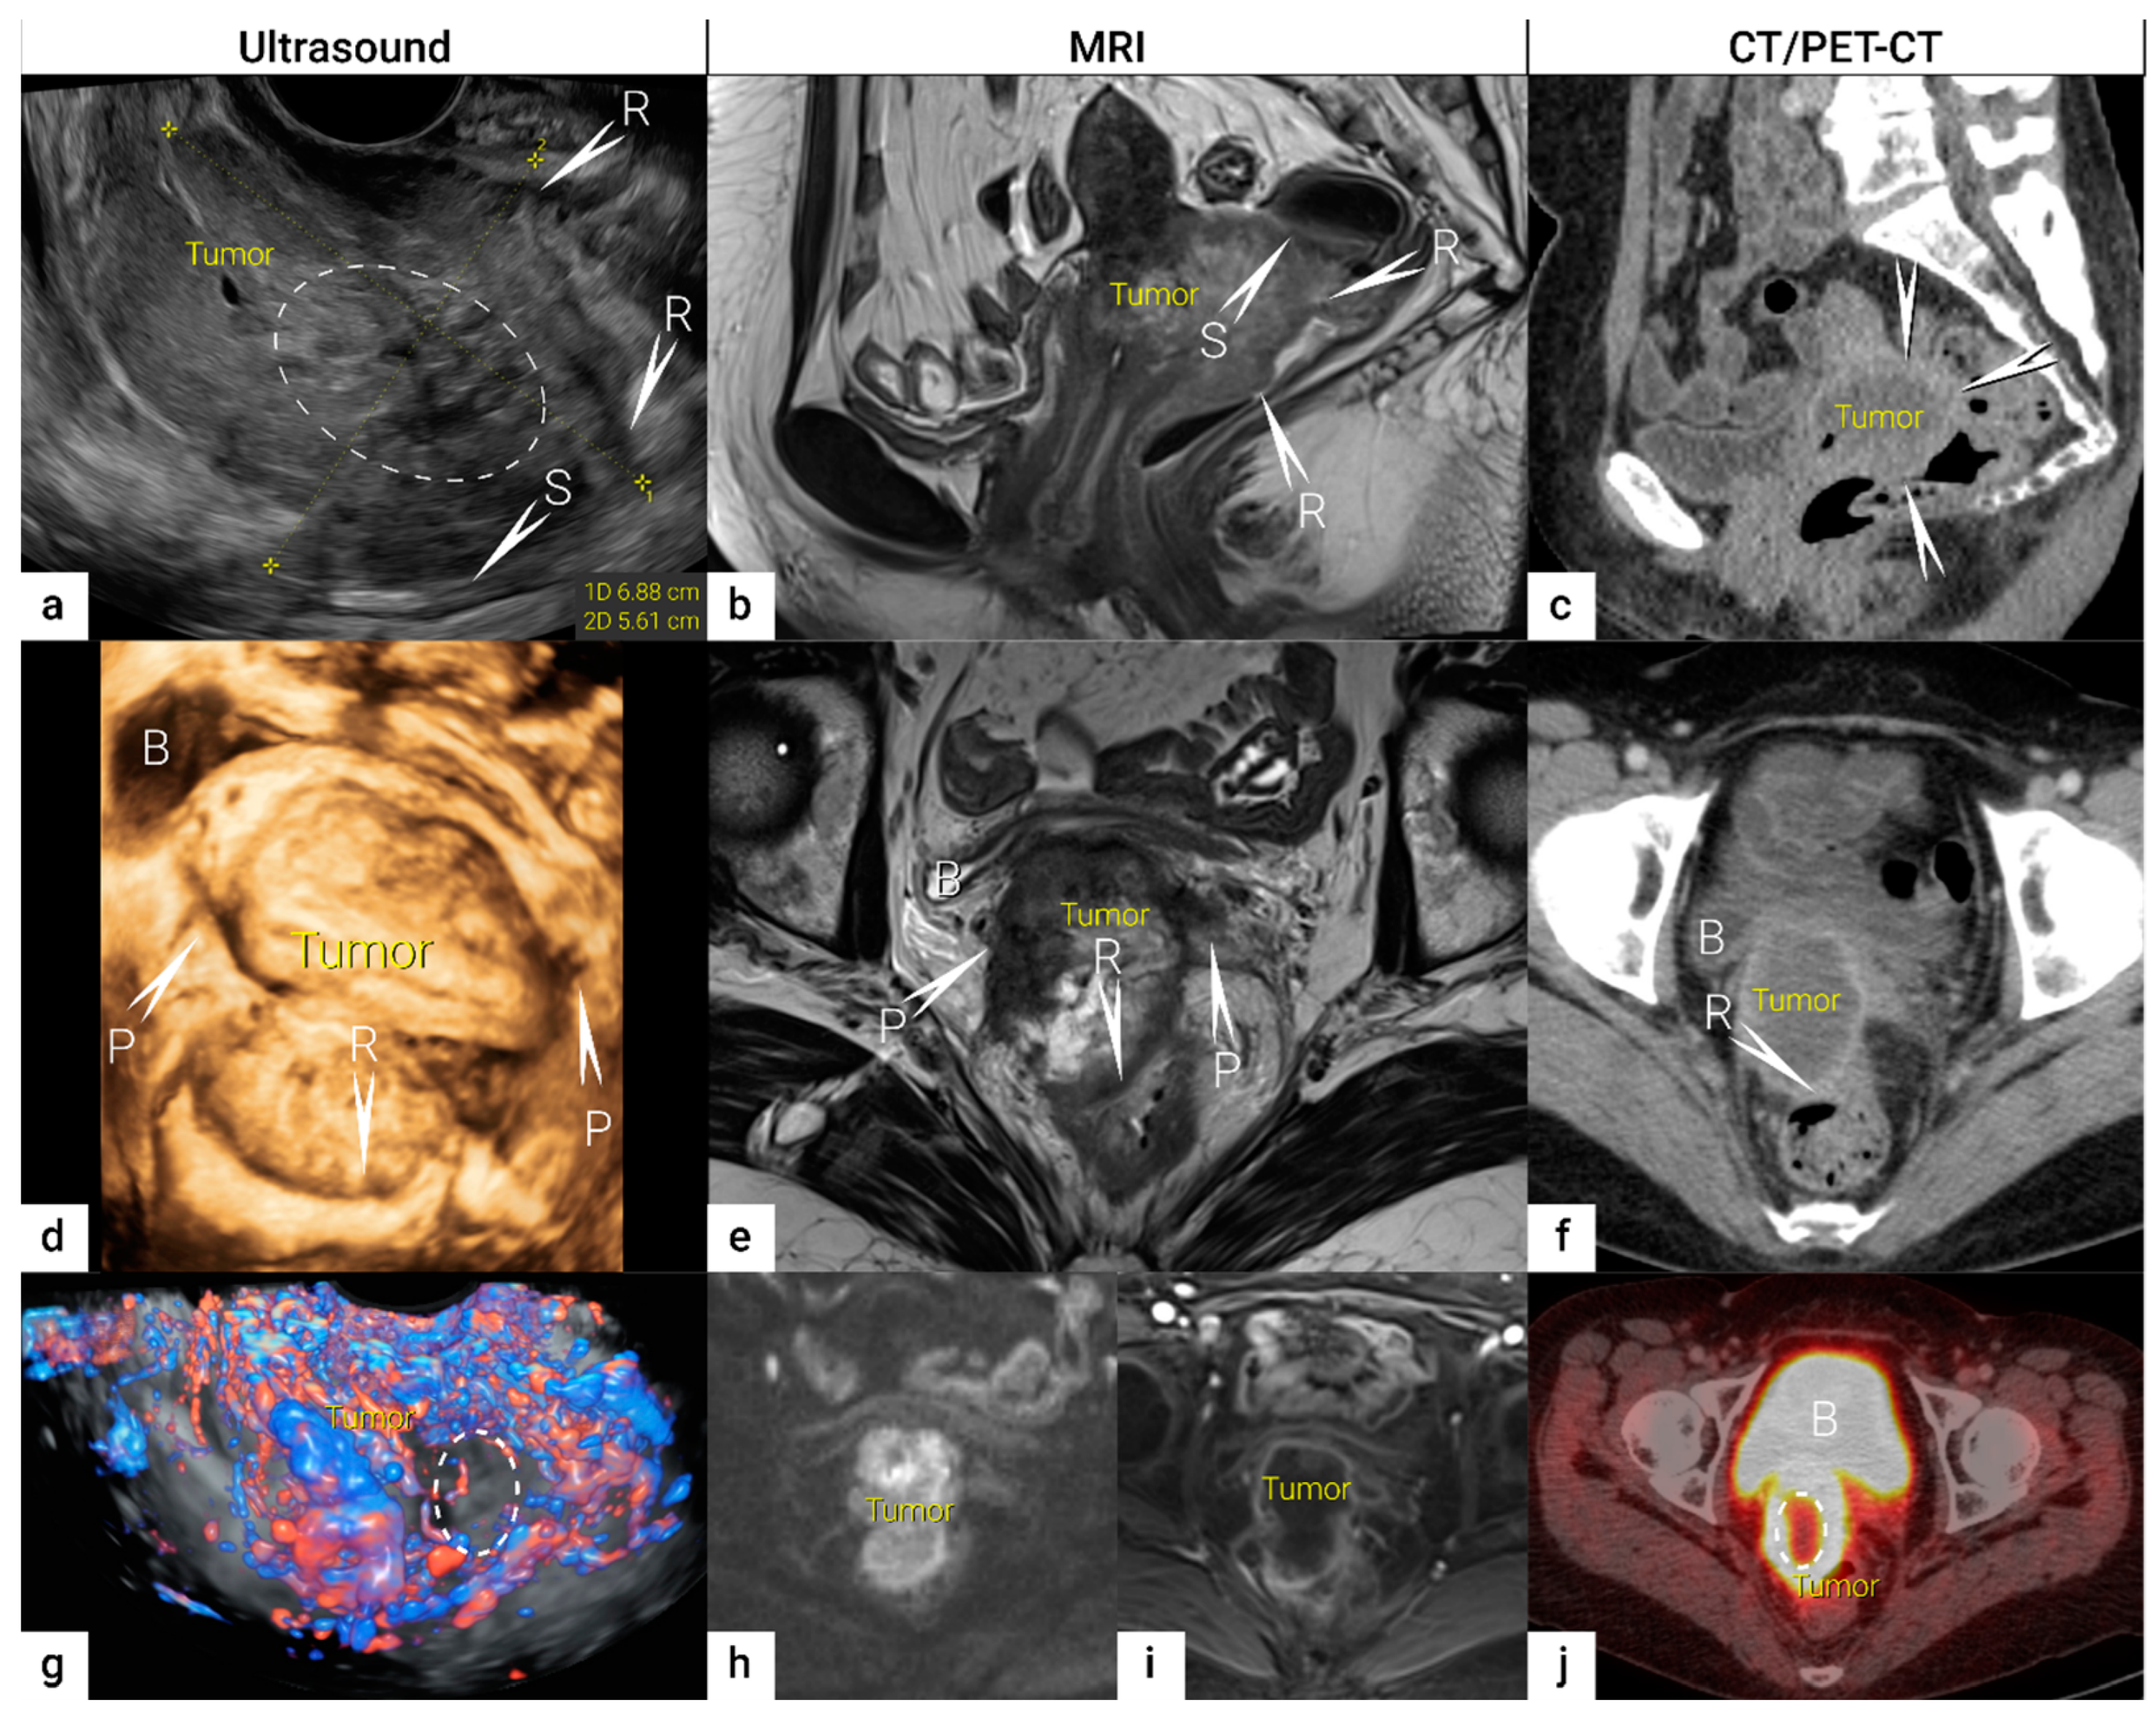

| IB | Carcinoma with deepest stromal invasion >5 mm, limited to the cervix uteri with size measured by maximum tumour diameter. | US: Highly vascularised hypoechogenic (squamous-cell carcinoma) or iso-/hyperechogenic lesion (adenocarcinoma) with intact hyperechogenic pericervical fascia and positive sliding sign between tumour and bladder/rectum. MRI: Tumour has intermediate to high signal on T2W images. Dynamic CE-T1W images depicts tumour as hyperintense in the arterial phase and iso- or hypointense in the venous phase. Tumours characteristically exhibit restricted diffusion on DWI (hyperintensity on high b-value images and low intensity on the ADC maps). Tumour does not disrupt the hypointense peripheral stromal ring (best seen on T2W images). | |

| T2b | IIB | Parametrial tumour invasion but no pelvic side wall extension | US: Tumour infiltrates the hyperechogenic pericervical fascia, negative sliding sign, presence of hypoechogenic tumour projections into hyperechogenic parametria. MRI: Tumour disrupts the hypointense peripheral stroma and extends into the parametrium +/− abutting parametrial vessels on T2W images. |

| T3 e | III e | Carcinoma involves the lower third of the vagina and/or extends to the pelvic side wall and/or causes hydronephrosis or non-functioning kidney | Tumour infiltration of the lower third of vagina or lateral pelvic side wall by US or MRI. Pelvic side wall infiltration is considered when the tumour causes hydroureter, infiltrates the obturator internus, piriformis, and levator ani muscles, encases the iliac vessels, or invades the pelvic bones on US or MRI. |

| T3b | IIIB | Tumour extension to the pelvic side wall and/or hydronephrosis or non-functioning kidney (unless known to be due to other cause). | US: Hypoechogenic tumour projections up to pelvic side wall +/− infiltration of iliac vessels, ureters, muscles, presence of hydronephrosis MRI: Hyperintense infiltration up to the pelvic side wall, loss of normal parametrial signal intensity and increased signal intensity in pelvic musculature due to tumour invasion seen on T2W-images. |

| T4 f | IVA f | Tumour invasion into the mucosa of the bladder or rectum (biopsy-proven) or into adjacent organs. | Tumour invasion into the mucosa of the bladder or rectum on imaging, confirmed by biopsy. US: Negative sliding sign, hypoechogenic tumour infiltration of bladder/rectal wall up to echogenic mucosa with polypoid tumour seen intraluminally. MRI: Focal or diffuse disruption of the normal T2-low signal intensity wall of the bladder/rectum, irregular or nodular wall, sometimes including an intraluminal tumour mass. Bulous edema sign, which is hyperintense thickening of the bladder mucosa on T2W images, is only an indirect sign of invasion and should not be regarded as T4 unless confirmed mucosal infiltration at cystoscopy. Infiltration of the posterior bladder wall without mucosal infiltration should not be regarded as T4a. |